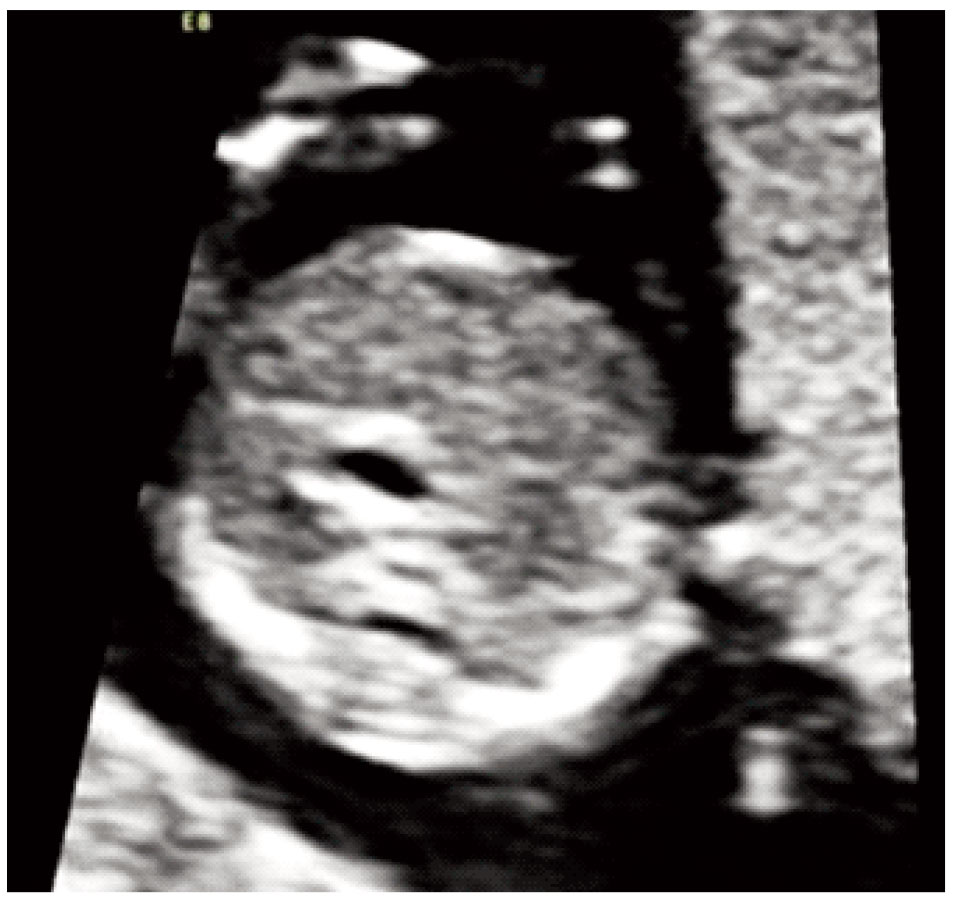

The stomach was present but located centrally rather than on the left side of the abdominal cavity (Figure 1). In addition the cardiac axis deviated to the left. Maternal biochemistry was normal (βhCG: 0.308 MoM, PAPPA: 0.518 MoM) and the risk for the common trisomies was low (1 in 11,941). Repeat ultrasound examination at 17 weeks showed that the stomach remained in central position, there was persistent left superior vena cava and the aorta had obviously smaller diameter than the pulmonary artery (Figures 2, 3). The results were confirmed by fetal echocardiography.Amniocentesis was performed at the request of the parents; the fetal karyotype was normal (46XY) and there were no additional findings from CGH arrays analysis. Fetal MRI at 24 weeks confirmed the central position of the stomach whereas no structural anomaly was detected. Repeat fetal echocardiography at 29 weeks showed normal growth of the aorta and the aortic arch, two morphologically left atria and interrupted inferior vena cava thus establishing the diagnosis of left atrial isomerism. Further investigations by Whole Exome Sequencing detected two missense variants of uncertain significance in the gene PKD1L1. Pathological mutations with heterozygosity in this gene have been associated with autosomal visceral heterotaxy. The parents were counseled by a clinical geneticist on the favorable prognosis in the absence of a heart defect and decided to continue the pregnancy. Repeat MRI scan at 35 weeks identified multiple small spleens and malrotation of the bowel.The infant was born by cesarean section at 38 weeks (birth weight 3,300 gr). The diagnosis was confirmed after birth. He is currently discharged at home and is scheduled for bowel surgery.

Figure 2. Cross‐sectional view of the fetal abdomen at 17 gestational weeks with the stomach positioned centrally.